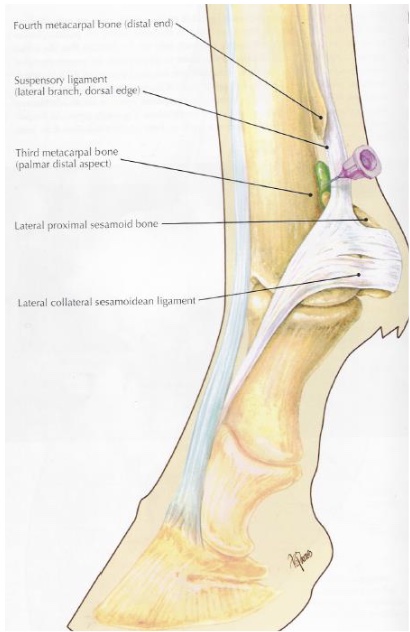

what is desensitized in a low 4 point nerve block (proximal to fetlock)

metocarpo(tarso)phalangeal joint & structures distal

distal aspects of suspensory branches

what is desensitized in an abaxial sesamoid nerve block “basisesamoid block”

foot, second phalanx, proximal interphalangeal joint, distopalmar/plantar aspect of proximal phalanx, distal portions of DDFT & SDFT, distal sesamoidean ligaments, digital annular ligament

v shaped area at front of P1 may not be blocked